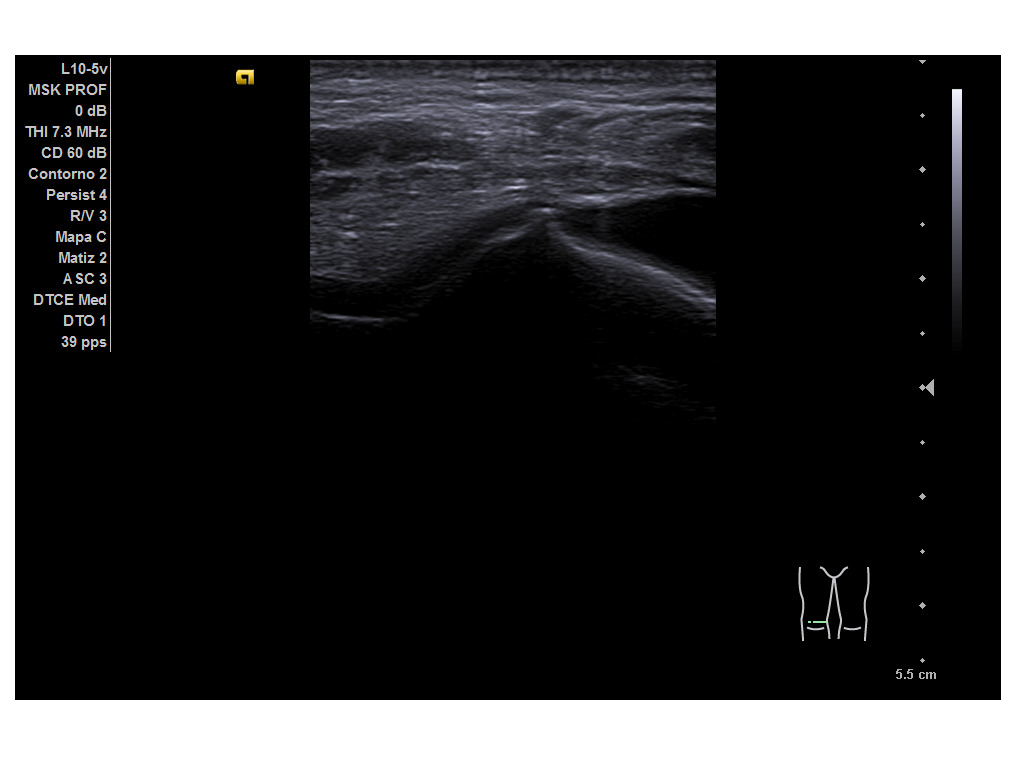

Durante la ecografía se observa una imagen anecoica suprarrotuliana, bajo el tendón del cuádriceps, compatible con una bursitis suprarrotuliana a nivel de la porción medial del cóndilo femoral medial de la rodilla derecha tanto en cortes transversales como longitudinales. Resto de las imágenes obtenidas se encontraban dentro de la normalidad.